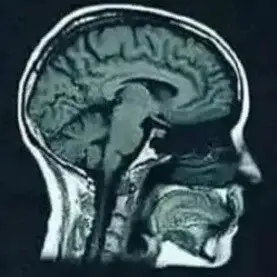

MRI scan (Magnetic Resonance Imaging) is a magnetic resonance scan. The MRI scan uses a magnetic field that is harmless, except if there are iron objects in the body or on the body. An MRI scan consists of a table on which the patient lies and a hollow cylindrical magnet. The cylinder is too frightening for many people and people who are seriously overweight do not fit in it. That is why MRIs are also made with two separate plates.

An MRI scan can show how many hydrogen nuclei are in one area. Each type of tissue has different hydrogen densities and thus details of the anatomy can be observed. A three-dimensional image is formed from the measurements.

An MRI scan can observe the brain structure, location, size, space-occupying processes, (brain tumors and inflammations) abnormalities of healthy tissue and scars (focal damage). An MRI scan cannot show axonal damage or diffuse axonal damage, or the latter with great difficulty as a white matter abnormality.